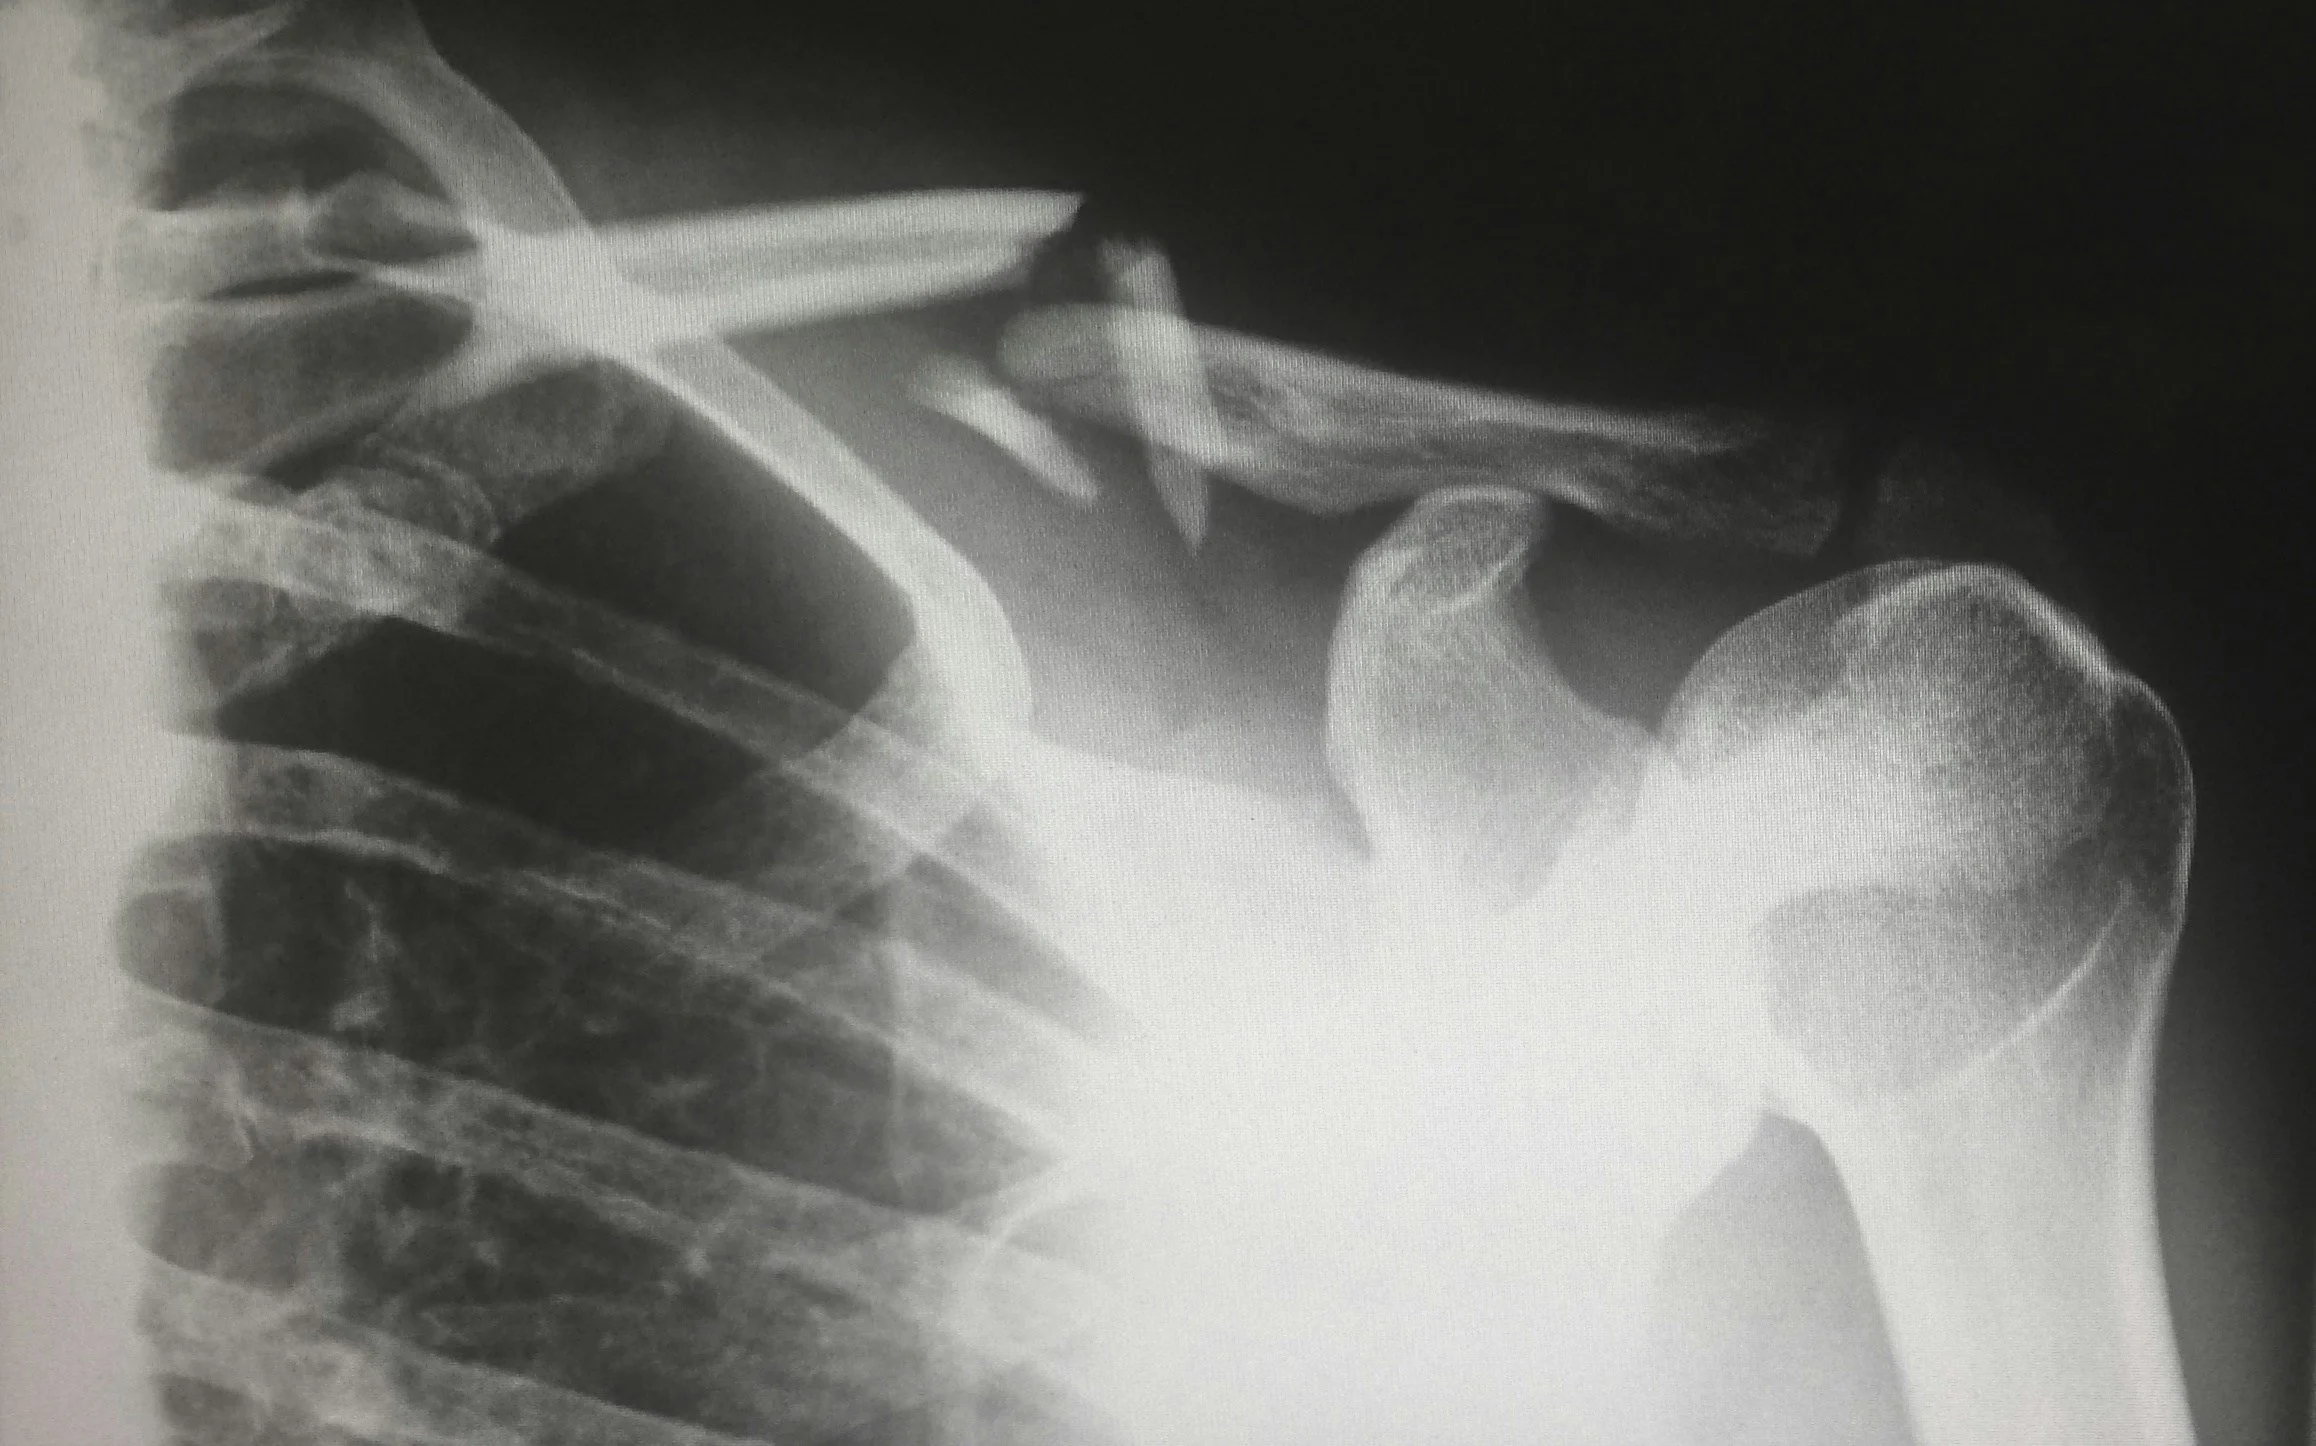

X-ray image showing a broken shoulder with fractured bones

An X-Ray is an imaging technique which uses a small amount of ionising radiation to create images of bone and other body structures. X-Rays are effective and safe; our staff take precautions to minimise radiation exposure. The entire procedure usually takes only a couple of minutes and is painless for the patient.

X-Rays are commonly used for detecting bone fractures and injuries, however, are also used for scanning the lungs, chest and other body structures like the heart and abdomen.